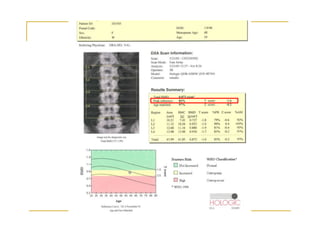

SITIOS A ANALIZAR

Cuello femoral

(izquierdo)

Columna lumbar

(L2-L4 ó L1-L4)

Score T: Valor de referencia de DMO de un grupo de

sujetos sanos de 30 años del mismo sexo

Score Z: Valor de referencia de sujetos de la misma edad

que el individuo en estudio

Criterios

NOF

AAEC

CLASIFICACIÓN OMS

NORMAL: T score hasta –1.0

OSTEOPENIA: T score entre –1.0 y –2.5

OSTEOPOROSIS:      T score menor a –2.5